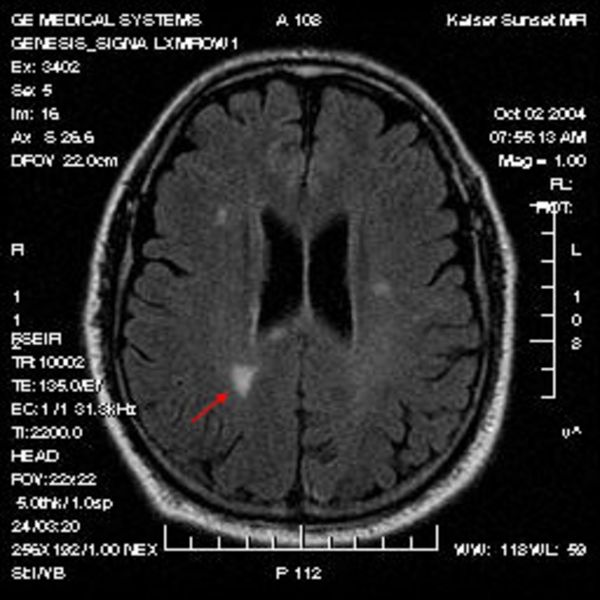

Multiple Sklerose